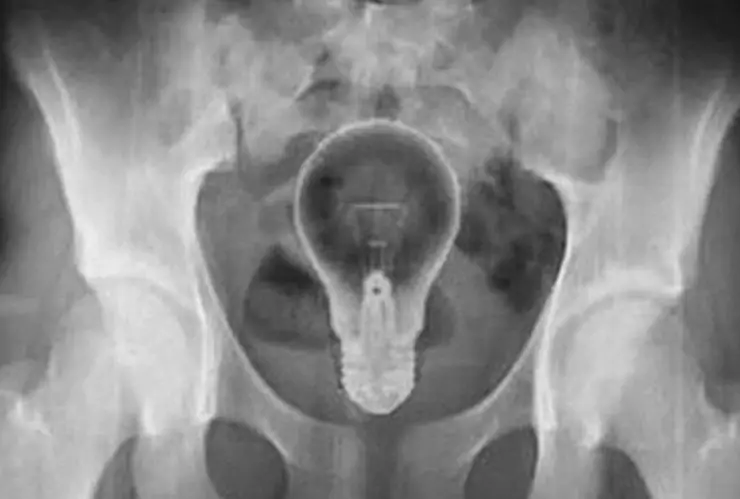

En los primeros estudios que le practicaron no encontraron la razón de los dolores que tenía el hombre, pero tras una radiografía pudieron ver lo que ocurría.

Los médicos localizaron un foco en el recto del paciente de 53 años de edad. La bombilla estaba a la altura del ano, según se ve en una imagen difundida en redes sociales.

Por suerte, la bombilla no se reventó porque era de plástico por lo que los médicos pudieron retirarle el objeto del ano.